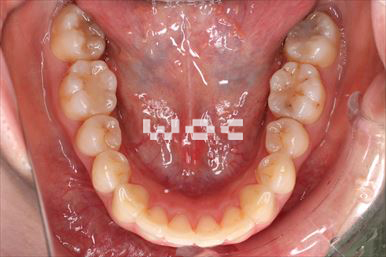

出っ歯エッジワイズ装置

特に装置の希望はなかったので、エッジワイズ装置を選択。

歯の移動量が大きいので歯根吸収の可能性がありましたが、目立った吸収は見られませんでした。-

治療中1

- 年齢:17歳女性

- 主訴:出っ歯、前歯のガタガタが気になる

- 基本矯正料金:78万円

- 治療期間:1年2ヶ月

- 抜歯部位:上顎両側第一小臼歯